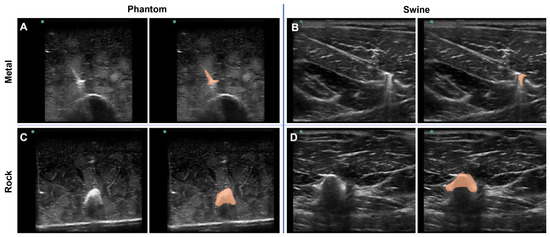

3.1. Overview of the Tissue Phantom for Shrapnel Image Acquisition

3.2. Application for Automated Shrapnel Detection

3.3. Phantom and Swine Training Datasets for ShrapML